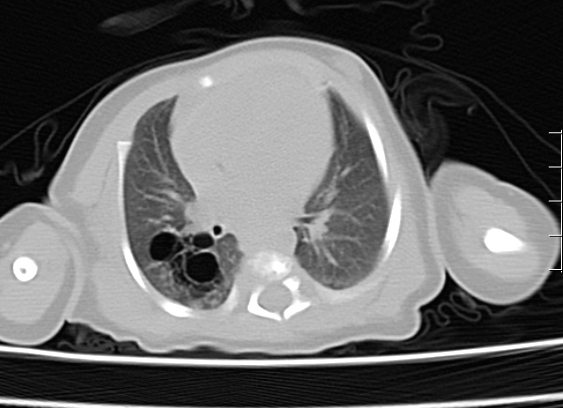

09-092024近日,我院PICU收治了一名先天性肺囊性腺瘤样畸形患儿,患儿母亲于孕22周产检时行超声检查发现胎儿存在该问题,胎儿期已诊断先天肺囊性腺瘤样畸形,在我院顺利生产,生后37天因并发感染于我院P...

09-022024近期我院PICU科收治了一名5岁患儿,这名小患者于兴城急诊转入我院,入院时患儿呼吸急促,鼻扇及三凹症明显,语颤,胸部皮下握雪感,经皮血氧饱和度85%,进一步完善胸部CT明确为纵隔气肿。纵膈...